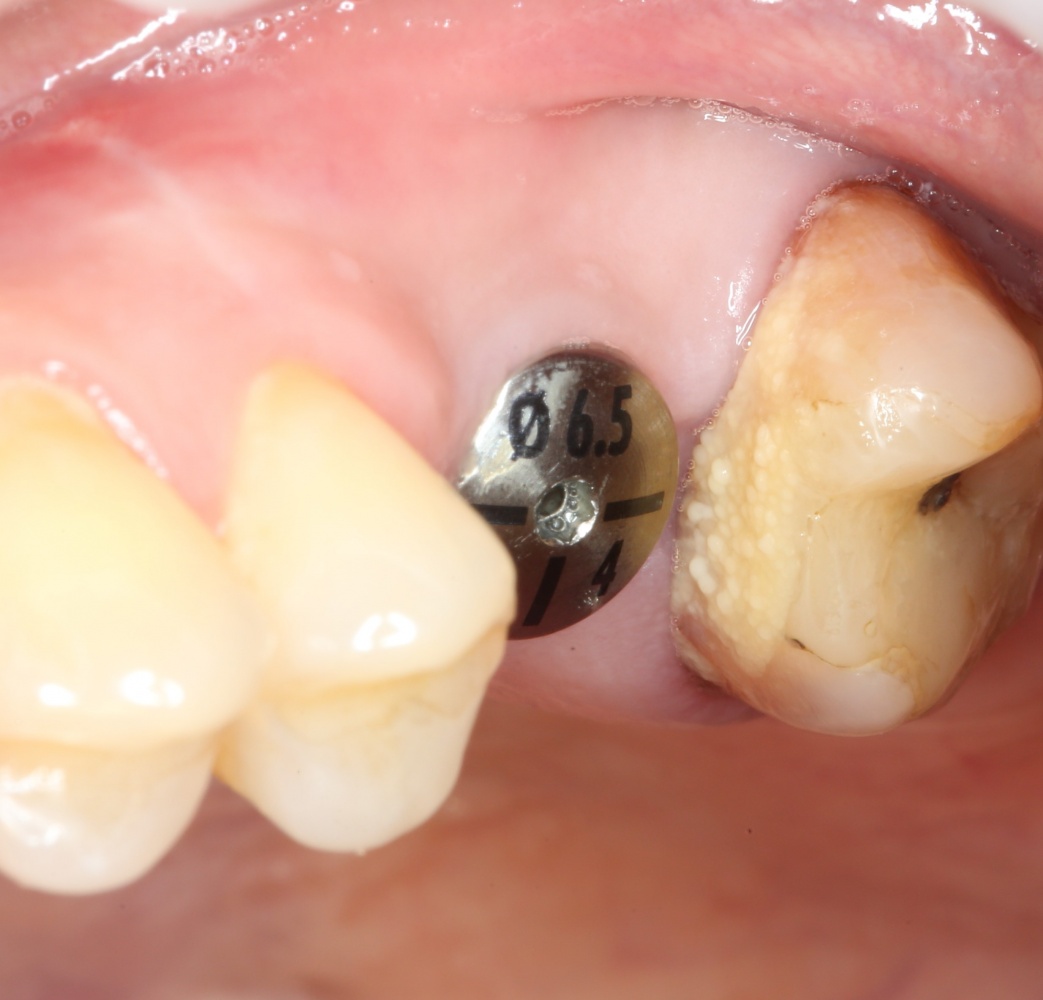

Вот ситуация:

По ряду причин, мы вынуждены удалить верхнюю шестерку и заменит ее на имплантат.

Все начинается с удаления зуба:

Обратите внимание на состояние вестибулярной стенки лунки. В проекции верхушек корней вы можете увидеть костный дефект, вызванный длительным воспалительным процессом (собственно, почему этот зуб пришлось удалять). В этом случае, вестибулярная стенка лунки неизбежно лизируется после удаления зуба, а это приведет не только к проблемам в эстетике, но и осложнит последующий уход за протетической конструкцией. Поэтому в данном случае мы должны продумать, в том числе, аугментацию лунки. И порядок действий здесь несколько иной, нежели в предыдущем случае.

Устанавливается имплантат Astratech (Dentsply Implants):